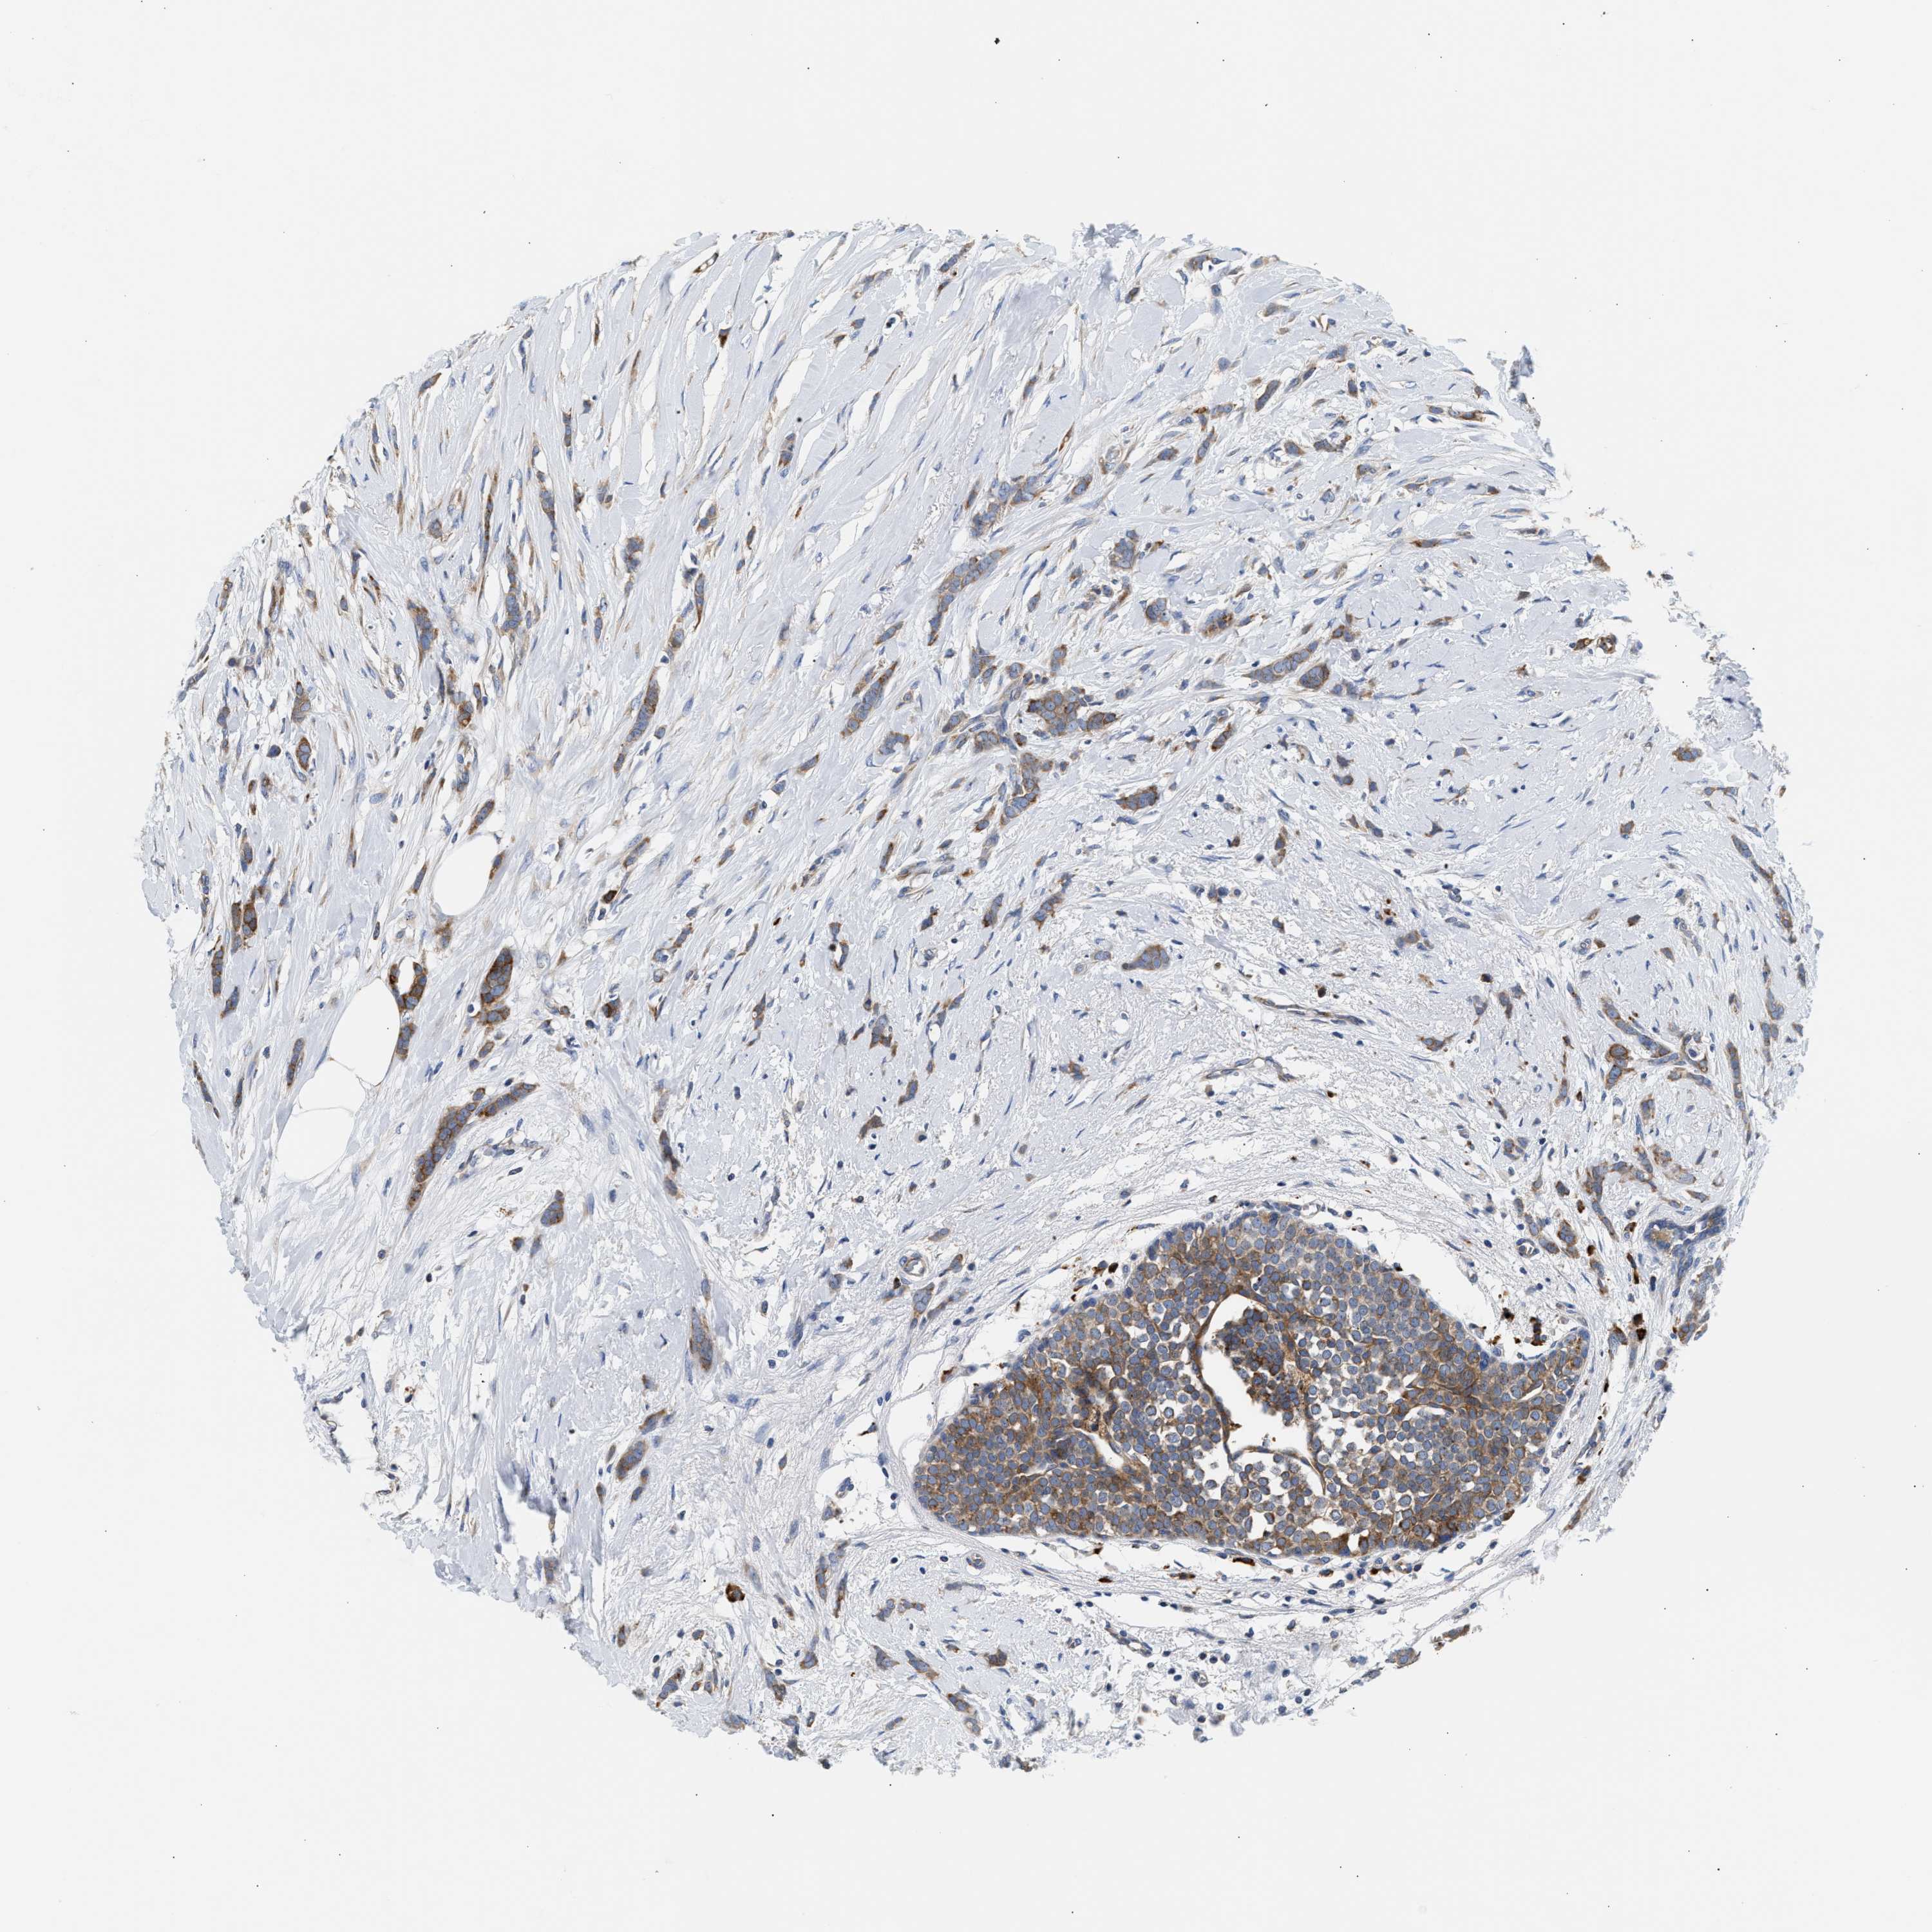

CANCER BREAST CANCER Show tissue menu

BRCA TCGA BRCA VALIDATION PROTEIN EXPRESSION

ANTIBODIES

AND

VALIDATION